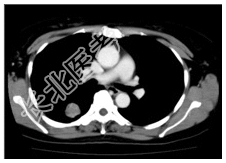

- [材料题] 患者,女性,47岁,体检发现右肺结节。查体:双肺呼吸音清,未闻及干湿性啰音。心脏体查无异常。行胸部CT平扫及增强。

- 简答题1、患者的诊断及依据是什么?

- 简答题2、鉴别诊断有哪些?